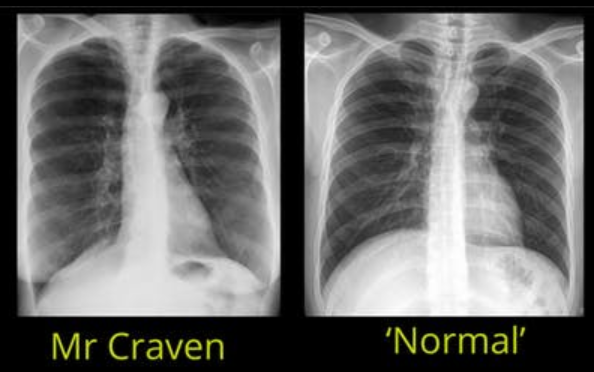

What are the differences between these 2 x-ray images?

Differences:

Flattened diaphragm

Heart looks smaller - more elongated and narrowed

More white / opaqueness at the bottom = breast tissue

Coming out of the vertebrae at the back = posterior rib, and followed around forms the anterior rib

Hyperexpanded chest - hyperinflation signs that can be seen on an x-ray, more than 7 anterior ribs visible at the midclavicular line, flattened diaphragm, heart may appear smaller and narrowed as the lung tissue has moved down as it so full and pulls down th eheart with it.